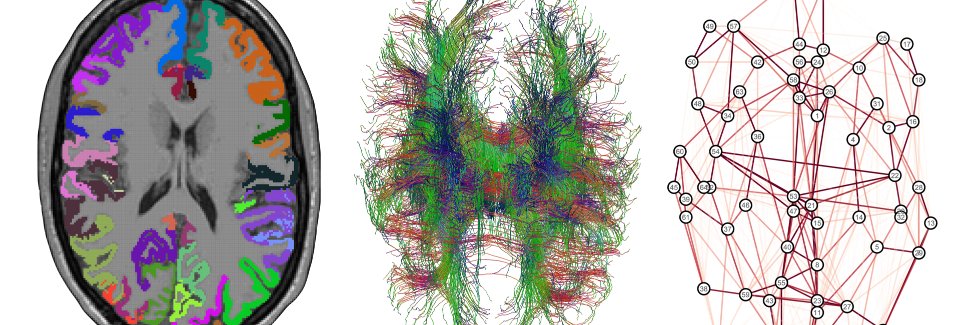

Developmental neuroscientist at @UCLchildhealth. European. Lib Dem councillor for Hitchin Highbury. Neuroimaging, R, language, education, politics. He/him